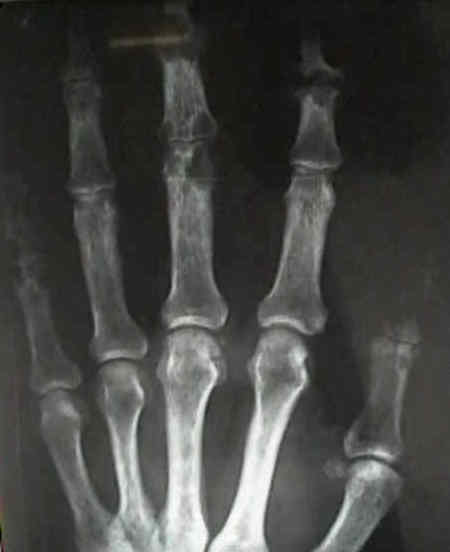

- in the hand look for oval periarticular erosions;

- multiple erosions will be distributed throughout the carpi and phalanges bilaterally;

- erosions have sclerotic borders and will often have overhanging edges;

- unlike classic RA, in early gout, hand and wrist joints will have preserved joint spaces and normal mineralization;

- example: